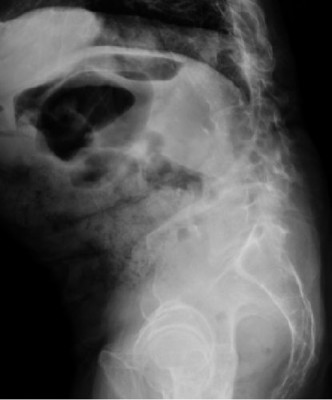

CASE 1 A 63-year-old male sustained a hyperextension injury to his neck while diving into a pool. Upon presentation, he reports decreased sensation in his hands and decreased strength in his arms and wrists, but no lower extremity complaints. On motor examination, he has 5/5 strength in his deltoids and elbow flexors and 4/5 strength in the elbow extensors, wrist extensors, and finger flexors. Lower extremity motor examination is normal. Sensation is decreased to light touch in both hands. Otherwise his sensation is preserved. Images of his cervical spine are shown in Figures 1–1 to 1–3.

Figure 1–1

The correct answer is (B). The clinical scenario describes a patient with central cord syndrome (CCS). CCS continues to be the most common incomplete spinal cord injury accounting for 15.7% to 25% of all spinal cord injuries. The characteristic presentation is an extension moment injury in a previously spondylotic and stenotic spine. Figures 1–1 to 1–3 demonstrate a spondylotic spine with central narrowing and CSF effacement that is worst at the C3–4 level. Bleeding, edema, and/or Wallerian degeneration lead to damage of the lateral corticospinal tract which is the main descending motor tract in the spinal cord. The more central anatomic position of the homunculus to the upper extremities places them at greater risk than those to the lower extremities. As such, injury to the lateral corticospinal tract is characterized by upper more than lower extremity involvement and motor deficits being more pronounced than sensory deficits.